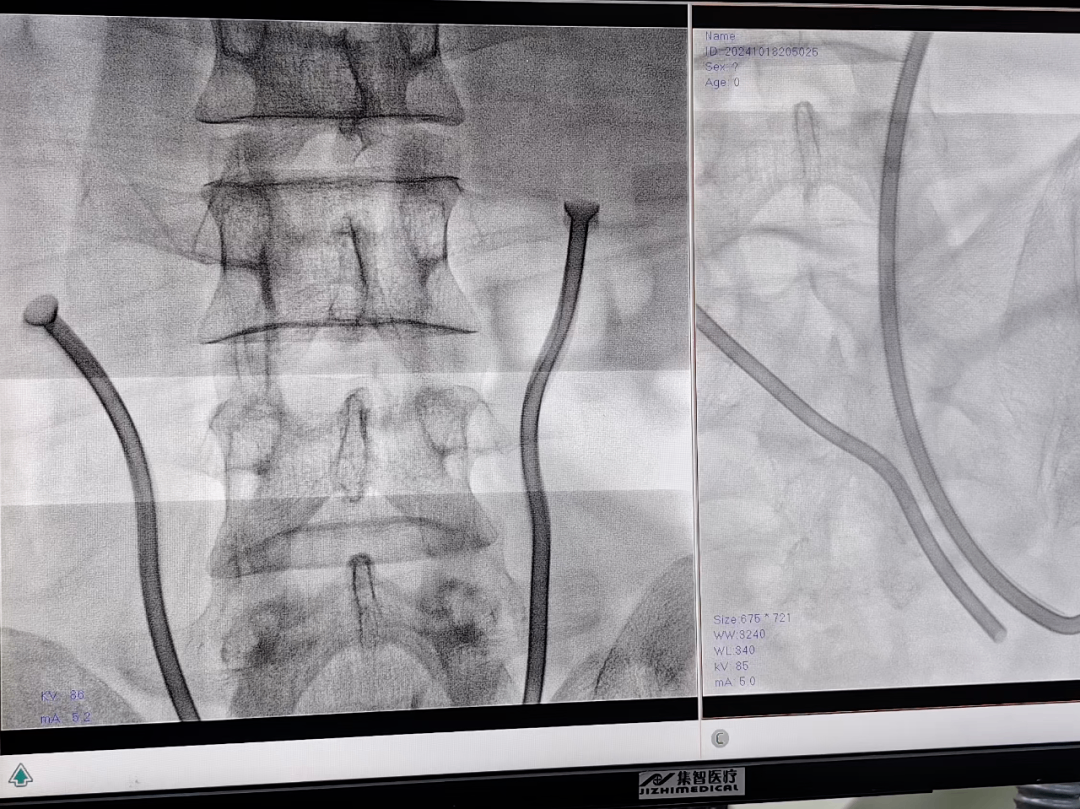

一位患者曾饱受双侧输尿管狭窄病痛折磨。此前因输尿管狭窄出现双肾积水、慢性肾功不全等问题,采用传统治疗方式效果不佳,还带来诸多困扰。后来,患者来到我院。经科内讨论,为其内置了梅莫凯斯新型热膨胀金属支架。这种支架可是全球唯一一款没有留置时间限制的尿路支架系统,不容易堵塞,无需反复更换。手术中,采用经皮肾镜顺行加输尿管镜逆行双镜联合,X 线及超声双定位,精准放置支架。注入 65℃热水后,镍钛合金支架成功膨胀,锚定于狭窄处,输尿管再度恢复通畅。

术后KUB所示

术后膀胱镜所示